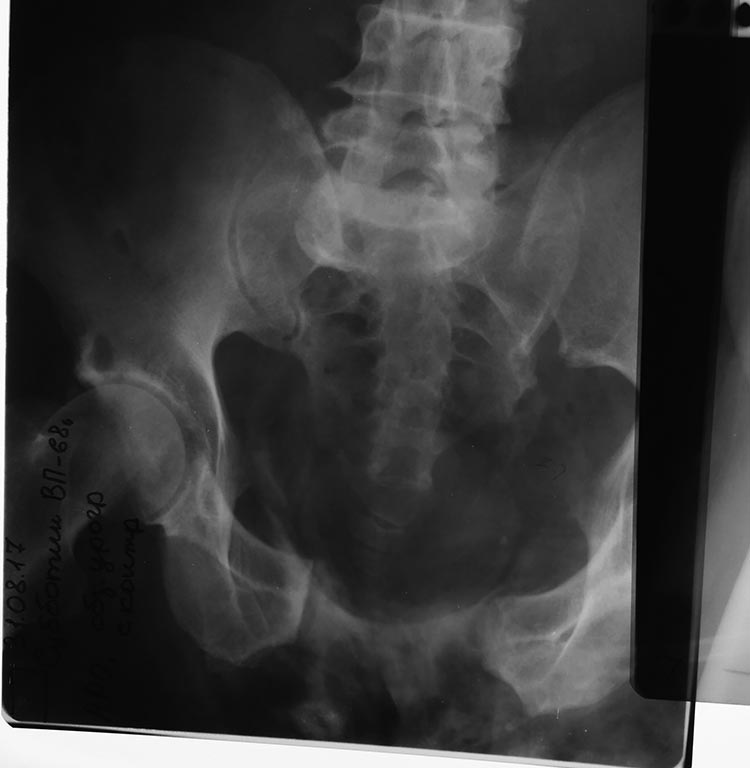

Поделитесь опытом. Больной М поступил в травм. отд. с

диагнозом: Сочетанная травма з.перелом Хир шейки плеча разрыв

крестцово-подвздошного сочленения, разрыв лонного симфиза. Разрыв уретры.

Как можно сопоставить таз? Попробовал закрыто с АВФ сопоставить,

результат ниже на фото, какие методы советуете?